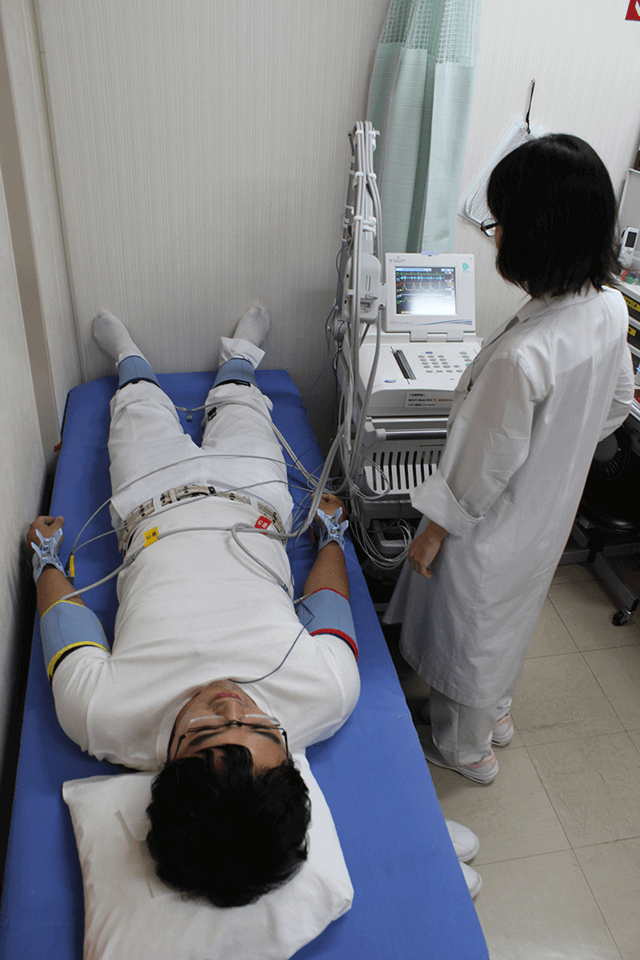

両腕・両足首の4箇所の血圧、心音、心電図を同時に記録し、CAVI(心臓足首血管指数)やABI(足関節上腕血圧比)を測定します。

CAVIは動脈の硬さ、ABIは下肢動脈の詰まりの程度を表し、動脈硬化の指標となります。

動脈硬化性疾患や末梢動脈疾患の早期発見に役立ちます。